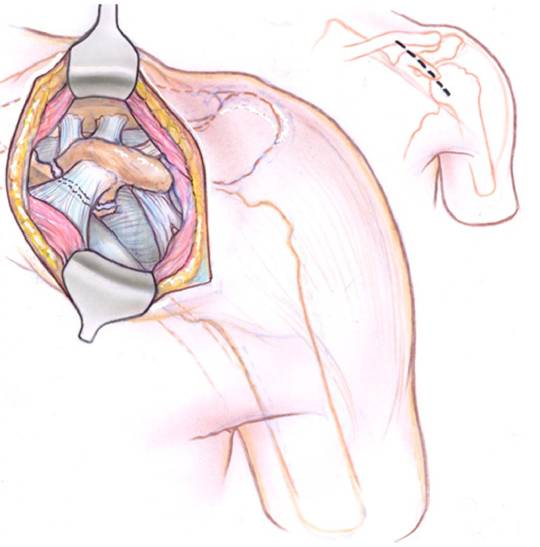

- 在骨折部位标记三角肌胸大肌肌间沟,触及喙突位置,沿郎格氏线垂直切开皮肤、皮下组织和锁胸筋膜。

解剖研究显示术中切口的解剖标志,经前方入路切开后通过Langer’s线分离显露喙突

- 喙突远端位于胸大肌和三角肌之间,由喙突向头侧锁骨端切开,从锁骨处到骨折处切开胸大肌,钝性剥离三角肌内侧大部分纤维,显露喙突和喙锁韧带的(圆锥韧带和梯形韧带)。

术中箭头所指的是CCL;CA表示喙肩韧带;CT表示联合腱

- 此时可以分辨出周围的韧带结构和附着点(喙肩韧带、联合腱以及喙锁韧带)。

通过前方入路可以清楚的显露骨折线和韧带的附着点。如果韧带完好,术中应该将韧带牵拉保护,以便对骨折进行解剖复位